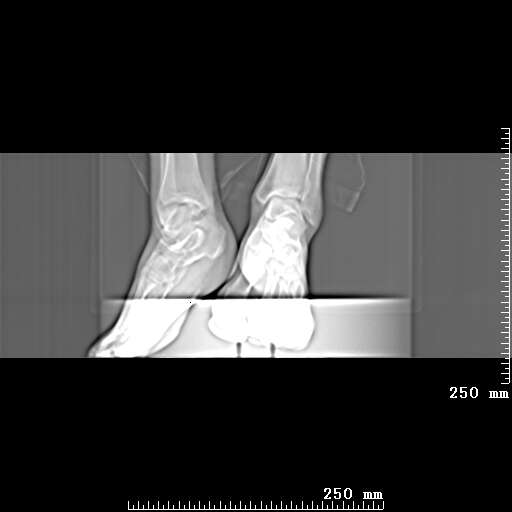

标题: CT19820:外伤一天,如何定性.男27Y [打印本页]

标题: CT19820:外伤一天,如何定性.男27Y

排除下创伤性关节炎吧,距骨有些囊变和硬化,周围韧带软组织有些机化、钙化。不是很像距骨无菌性坏死,感觉在关节面上的多,而不是距骨里面。

未见骨折及脱位像。距骨像是剥脱性软骨炎

支持!(踝关节距骨表面囊变和硬化 缺损)

距骨剥脱性软骨炎可能;踝关节创伤性关节炎?

未见明确新鲜骨折改变,距骨剥脱性软骨炎或踝关节创伤性关节炎可能。

距骨像是剥脱性软骨炎

关节周围多发高密度影,要结合病史